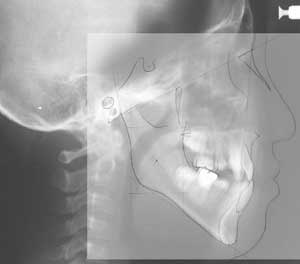

頭部X線規格写真(セファログラム)

X線の光源と被写体(人物)およびフィルム面までの距離が一定の条件の下に規格されており、同じ条件で客観的に本人と正常者との比較あるいは本人の経時的変化 (成長変化や治療による位置の変化)を比較することができます。